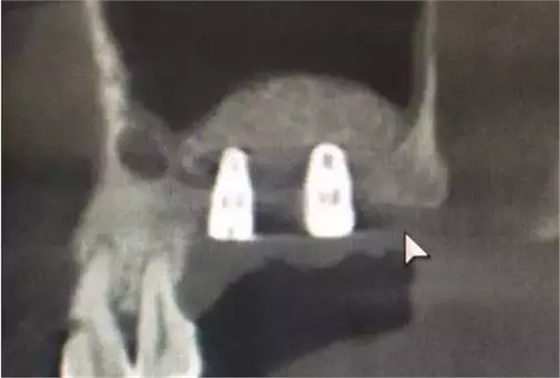

植入兩顆植體。

術后6,7牙位CT片,顯示充足的植骨量。

整個手術時間僅20分鐘,充分體現了:安全、方便、快捷的原則。